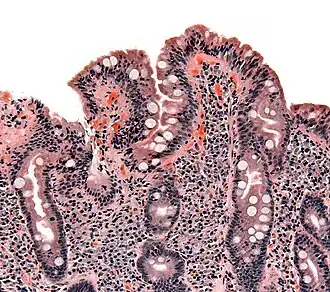

Biopsie van de dunne darm met coeliakie in Marsh-fase 3 met partiële of volledige villusatrofie wat zich uit in aftopping van de darmvlokken, crypt-hyperplasie en lymfocyt-infiltratie van de crypten. (Een crypt is een darmsapklier.) | ||||

Marsh Classification

De klassieke pathologische veranderingen bij coeliakie kunnen gecategoriseerd worden volgens de "Marsh Classification" [7]:

- Marshfase 0: normale mucosa

- Marshfase 1: toegenomen aantal intra-epitheliale lymfocyten, gewoonlijk meer dan 20 per 100 enterocyten

- Marshfase 2: proliferatie van de crypten van Lieberkühn

- Marshfase 3: partiële of volledige villusatrofie

- Marshfase 4: hypoplasie van de dunnedarmarchitectuur

Deze veranderingen verbeteren of verdwijnen compleet nadat een glutenvrij dieet wordt gevolgd.